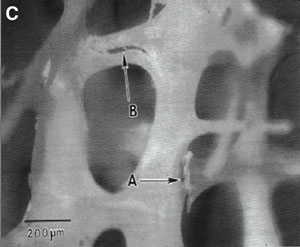

![]() |

C. Microcracks in the trabeculae (arrows) (reprinted from Fyhrie and Schaffler, 9 with permission from Elsevier). |